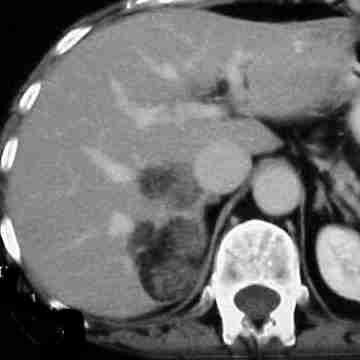

- Diaqnozu dəqiqləşdirmək üçün Qc venaları yoxlanılmalıdır. Bunun üçün dopler USM, KT-angioqrafiya, MRT-angioqrafiyalar və ya kontrastlı venoqrafiya edilir.

- Görüntüləmədə Qc venalarının trombotik tutulması diaqnozu dəqiqləşdirən əlamətdir.

PVT diaqnozunu dəqiqləşdirmək üçün portoqrafiya aparılır – Doppler USM, KT və ya MRT angioqrafiya.

- Kontrastlı müayinələrdə damarda tromb və ya kavernoz transformasiya

Baddi-Kiari sindromu böyük qaraciyər venalarının tıxanması nəticəsində meydana gələn venoz durğunluqdur, qaraciyər venaları ilə yanaşı aşağı boş venada da tıxanma ola bilir. Tromboz, fibroz, membran və infiltrasiya (şişlər, iltihab) ən çox rast gələn səbəbləridr. Erkən mərhələlərdə kəskin hepatit və kəskin qaraciyər yetməzliyi, xroniki mərhələdə sirroz və PH meydana gələ bilir. Diaqnozu üçün tomoqrafiya və kontrastlı angioqrafiya lazım gəlir, Qc venalarının trombotik tutulması diaqnozu təsdiqləyir. digər xarakterik əlaməti birinci seqmentin hipertrofiyasıdır. Erkən mərhələdə dekompressiya (cərrahi və stend) sirroz əmələ gəldikdə isə transplantasiya ön planda tutulur.

Qaraciyər venalarının görünməməsi, kontrastlaşmaması və ya trombla tıxanması.

- portoqrafiyada vena mənfəzində trombun görünməsi;

- venanın distalında genişlənmə və kavernoz transformasiyanın görünməsi;